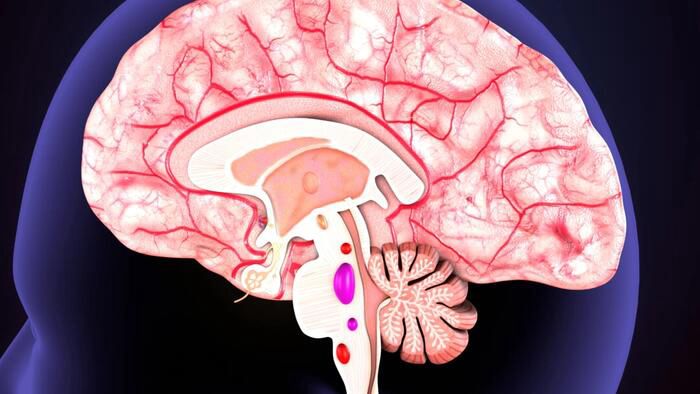

Several Common Drugs Are Linked To Dementia | ZeroHedge

Several Common Drugs Are Linked To Dementia | ZeroHedge